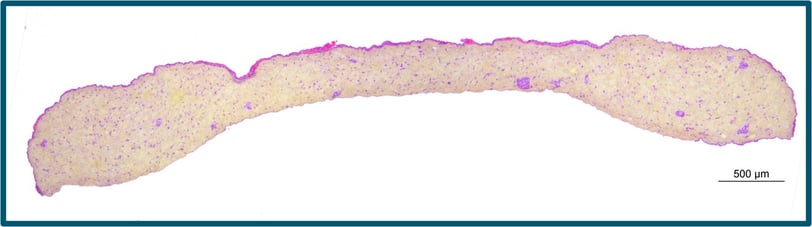

CTIBIOTECH was one of the rare companies to be awarded an iDEA-iTECH Award from the SANOFI corporation, late in 2023. This fast forwarded our program to make the world's first artificial skin for vaccine testing. Working together with SANOFI advanced scientists we were able to validate our work.